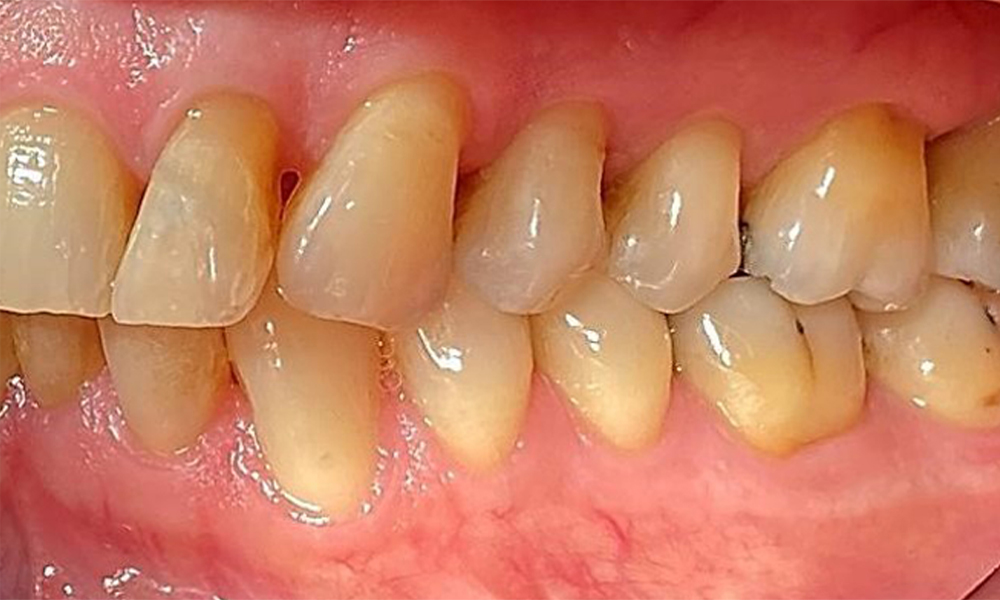

The patient has a full dentition with 28 teeth, which includes amalgam and composite fillings in the molar and premolar regions. There is a visible clinical marginal gap present on tooth 14. Tooth 27 has an adequate gold inlay. There are also generalized attritions and abrasions. (Fig. 2, Fig. 3, Fig. 4, Fig. 5, Fig. 6)

The patient has stage II, grade B periodontitis (5). At 1 to 3 mm, the clinical probing depths were within the physiological range. Localized probing depths of 5 mm were observed on the mesiopalatal aspects on both 17 and 27. There are generalized recessions of 1–3 mm with partial loss of the interdental papillae (Fig. 2, Fig. 3, Fig. 4)